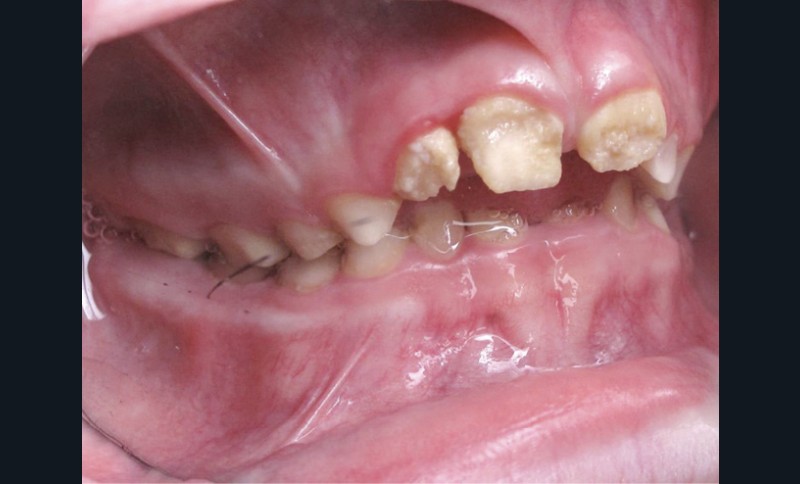

Il existe des anomalies dentaires (tabl. I) [1-12], mais aussi occlusales associées aux AI (fig. 1 et 2).

Selon de nombreuses études, l’anomalie occlusale la plus fréquemment retrouvée en association avec les AI est l’infraclusion antérieure, puisqu’elle est retrouvée chez 22 à 64 % des patients présentant cette affection, et encore plus chez les femmes [2,8,13-19]. Cette anomalie touche tous les types d’AI mais à des degrés très divers. Son incidence semble élevée dans les formes hypominéralisées, moindre dans les formes hypoplasiques et nettement moindre dans les formes hypomatures [8,17,18]. La sévérité de l’atteinte amélaire ne semble pas corrélée avec la présence ou l’intensité de cette malocclusion [17].